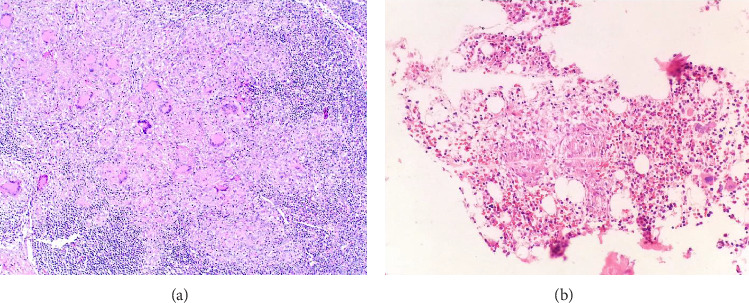

Introduction: Tuberculosis (TB) is a prevalent disease in Guatemala, present in 20-25 cases per 100 thousand inhabitants. Extrapulmonary TB (EPTB) accounts for only 10%-17% of TB cases. The diagnosis of EPTB is challenging, especially in low-resource settings, because TB can present with clinical characteristics of rheumatological, oncological, or other infectious diseases. Occasionally, mycobacterial infection stimulates the immune system, inducing the generation of antibodies that may lead to autoimmune diseases secondary to primary TB infection, such as vasculitis. To the best of our knowledge, no data have been reported on the prevalence of vasculitis, although some studies worldwide have determined that small-vessel vasculitis is the most common. Here, we present a case report of a male patient with EPTB diagnosed with Microscopic polyangiitis (MPA). Methods: A 17-year-old boy with no past medical history visited the emergency room with a three-day history of gastrointestinal bleeding. During hospitalization, acute kidney injury (AKI), disseminated lymphadenopathy, imaging studies, renal biopsy, and immunological tests were performed to confirm the diagnosis. Results: Endoscopy revealed a duodenal lesion containing Mycobacterium TB DNA. Further investigation of AKI led to autoimmune serological tests and kidney biopsy, confirming the diagnosis of antineutrophil cytoplasmic antibodies (ANCA)-positive pauci-immune GN. The patient was treated with antituberculous agents, steroids, and plasmapheresis. However, he developed alveolar hemorrhage and respiratory failure leading to death. Conclusion: TB is a common disease in low-income countries, with the pulmonary form being the most common presentation; however, the bacteria can spread to any organ, known as EPTB. It is important to consider that the inflammatory reaction associated with any form of TB can generate other types of noninfectious inflammatory diseases, such as ANCA-positive pauci-immune GN.